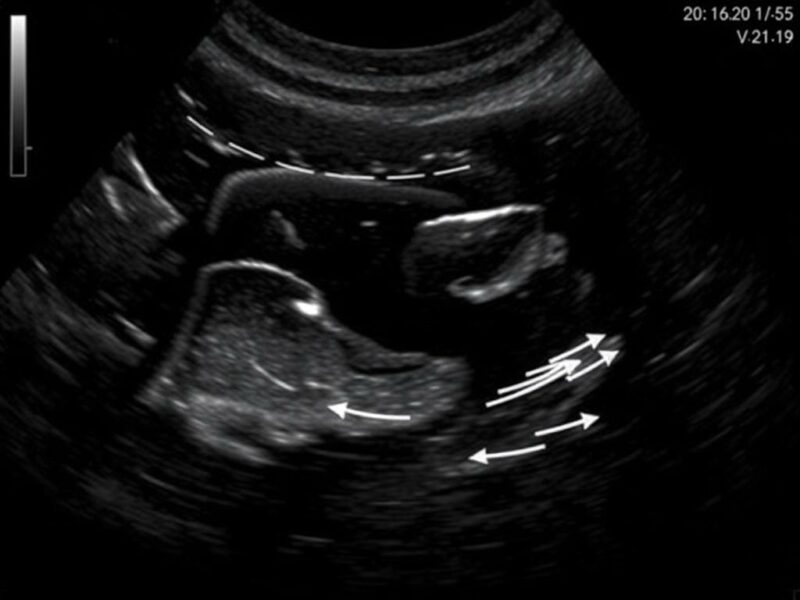

Uso del Doppler y hallazgos que refuerzan el diagnóstico

El Doppler color o power Doppler amplía la información: una pared apendicular con aumento del flujo vascular es un indicador de proceso inflamatorio activo. La hiperemia mural suele acompañar a la apendicitis aguda; en contraste, un apéndice crónicamente obliterado o fibrosado puede mostrar ausencia de flujo. No obstante, la interpretación del Doppler también exige cautela: el ajuste inadecuado del equipo puede tanto enmascarar flujo real como producir artefactos.

Cómo optimizar el Doppler

- Bajar la escala de velocidad y aumentar la ganancia de Doppler para captar flujos lentos.

- Utilizar power Doppler si se sospechan flujos de baja velocidad.

- Comparar con órganos adyacentes y con el ciego para detectar aumento relativo del flujo.

- Documentar imágenes en reposo y con respiración, evitando presión excesiva que reduzca la perfusión.